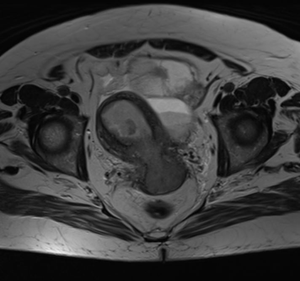

МР-диагностика рака тела матки

МР-диагностика рака шейки матки

МР-диагностика рака яичников